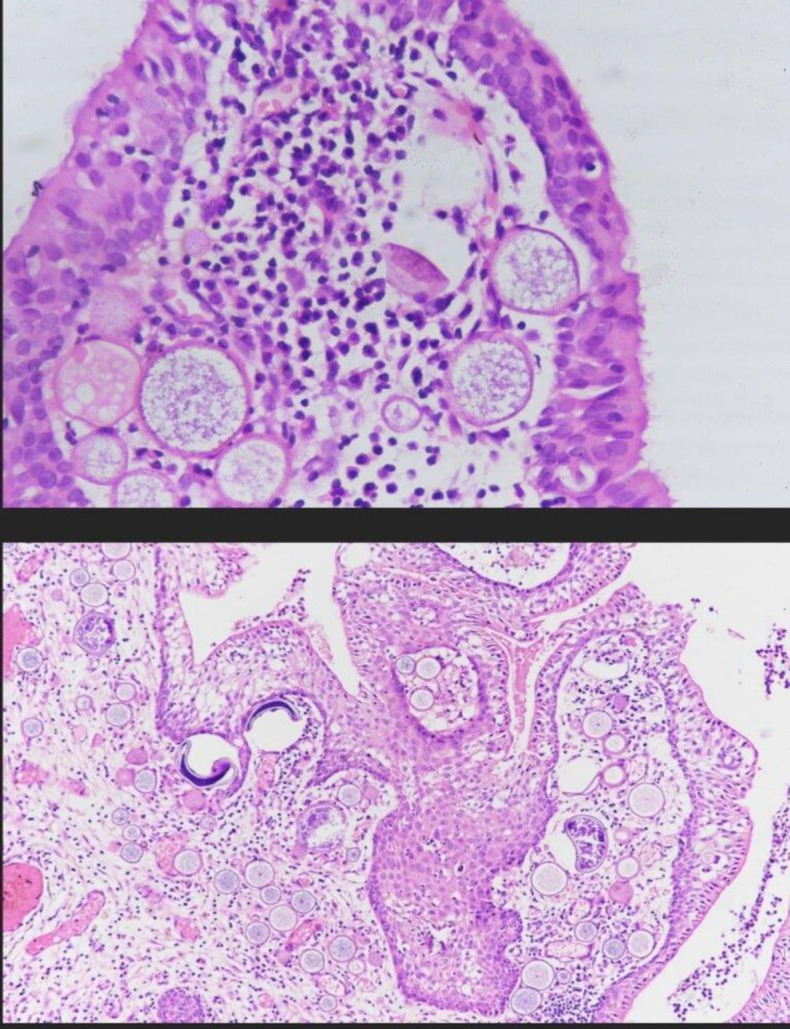

Introduction: Rhinosporidiosis is an enigmatic disease with many unsolved queries right from taxonomy to treatment. This study has been done to understand the disease characteristics with a peek into the lesser known immunological aspects of it by studying the changes in levels of certain primarily cell-mediated immunity (CMI)-specific cytokines in rhinosporidiosis patients.

Results: Disease showed male predominance and all patients gave a universal pond bathing history. Majority patients had O+ve blood group. Right side was affected most with nasal obstruction being commonest symptom. Nasal cavity was involved in majority of cases with inferior turbinate and meatus being sites of maximum occurrence and attachment. Nasopharynx, oropharynx were other involved sites. Extra-nasal sites included skin and parotid gland. Endoscopic and CECT findings were similar and confirmed intraoperatively. Tests for inflammatory markers showed no significant change in patients. Immunological markers -IL-6, TNF-beta- levels showed significant increase though no such increase was found with IFN-gamma levels.